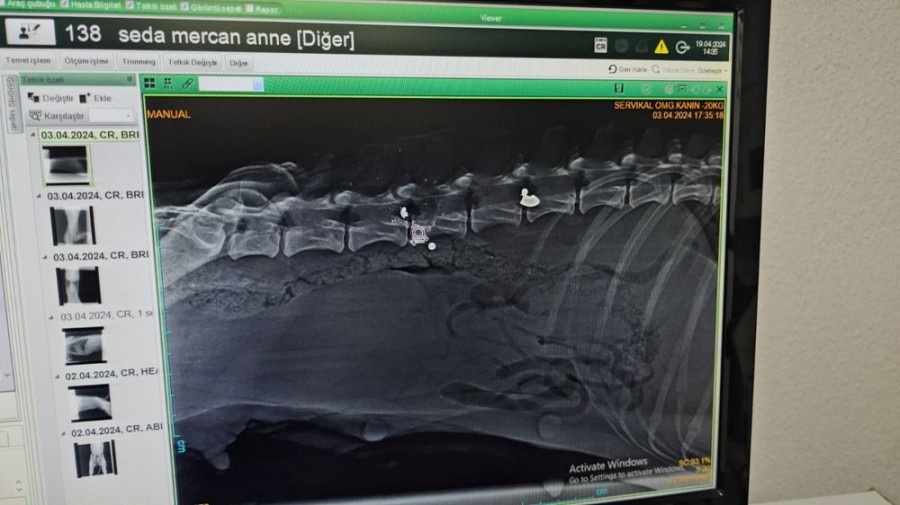

YAKIN MESAFEDEN ATEŞ EDİLMİŞ

Köpeğin yaralı, yavruların yeni doğmuş olarak geldiğini ifade eden Veteriner Hekim Ömer Faruk Alkan, "Röntgeni çekip muayene yaptıktan sonra yakın mesafeden ateş edildiğini, saçmaların omuriliğin içine ve vücuduna saplandığını gördük. Omuriliktekini arka tarafı felç kalacağı için saçmayı bulup çıkarttık. Omuriliğin etrafındaki kemik dokusunu serbestleştirerek oradaki sinirin baskısından kurtardık. Sonra yavrularının yanına koyduk." dedi.